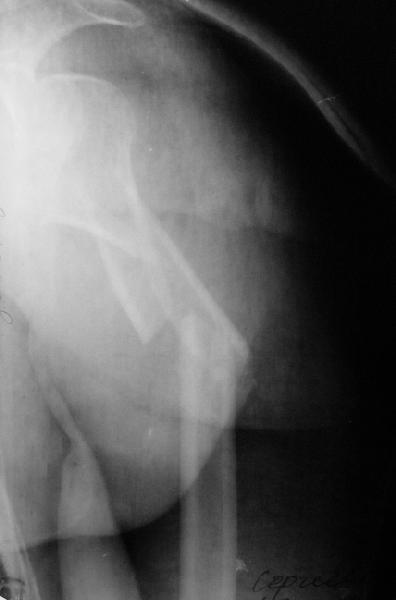

Мужчина 44 л. упал с крыши дачи 6 августа. Картиник в приложении. Лет

5 назад нде-то оперирован по поводу привычного вывихв этого же плеча.

После операции не вывихивал до этой травмы.

Как тут лечить? Есть ли шансы на закрытое вправление? Чем лучше

фиксировать? Какие меры принять с учетом бывшего и нынешнего вывиха?